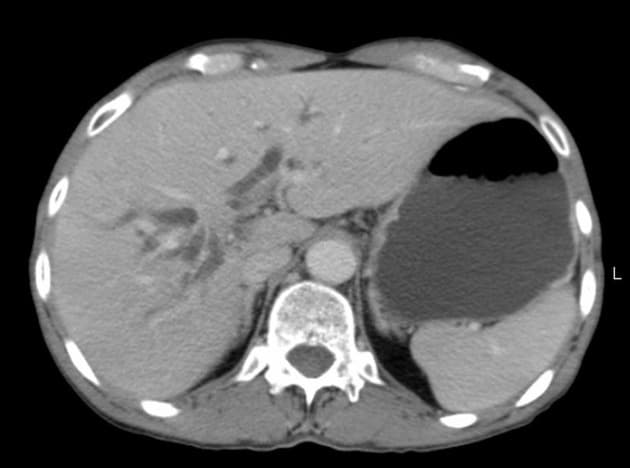

- Có giãn dạng thoi các ống mật ngoài gan (bao gồm ống mật chủ và ống gan chung) chứa nhiều ổ giảm tín hiệu trên mọi chuỗi xung, phân bố theo trọng lực, phù hợp với hình ảnh sỏi.

- Không có giãn đường mật trong gan.

- Có một tổn thương nhỏ dạng nang (tín hiệu cao trên T2, thấp trên T1 và không ngấm thuốc) ở đầu tụy, thông với một nhánh ống tụy nhỏ, phù hợp với IPMN nhánh bên (side branch IPMN).

- Không giãn ống tụy chính.

- Không thấy thành phần tăng mật độ có ngấm thuốc.

Interpretation: U nang ống mật chủ (type 1) kèm theo tổn thương IPMN nhánh bên phát hiện tình cờ (incidental side branch IPMN).

U nang ống mật chủ - type I (choledochal cyst - type I)